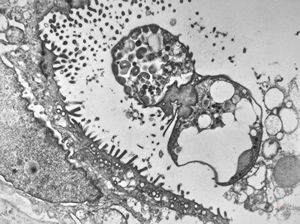

M,33y. | microsporidiosis (or cryptosporidiosis) - duodenum-posttransplantation immunodeficiency (HE and semithin section)

M,33y. | microsporidiosis (or cryptosporidiosis) - duodenum-posttransplantation immunodeficiency